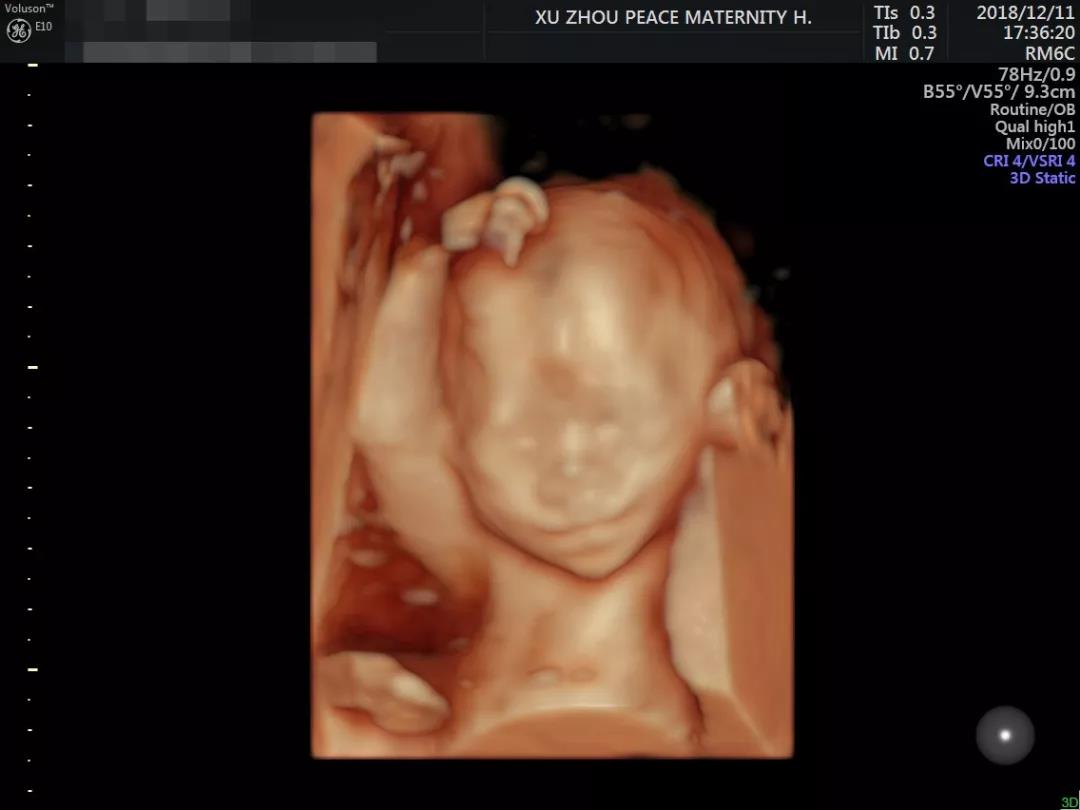

你如果看过邱博士做出的彩超图片

就明白为啥预约这么火爆了

▼

邱博士细致、严谨的工作态度再加上

操作美国GE-E10彩超设备的精湛技术